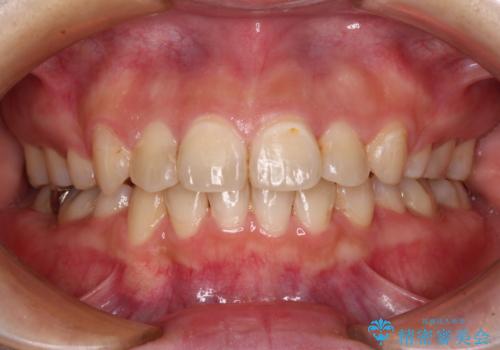

咬合力の緩和と食いしばりがちな咬み合わせが改善され、顎の負担が大幅に軽減されました。

- 食いしばりが気になっていたとのことで来院された患者様です。

当初は睡眠時のマウスピースのみの製作をご希望でしたが、矯正治療の提案をしたところ、インビザラインにて矯正治療を行うこととなりました。